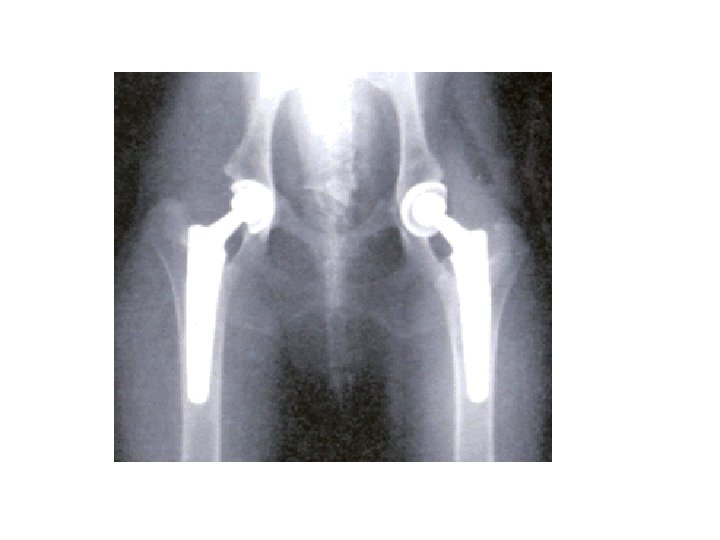

Наиболее часто остеоартроз поражает суставы üТазобедренный üКоленный üСуставы позвоночника üПлечевой сустав üМелкие суставы кистей рук и ног

Методы лечения остеоартроза üНемедикаментозный ü Медикаментозный ü Хирургический